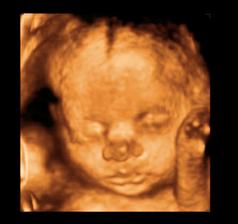

26 tt../1.4.2009/ naša paulínka je stráášne zlatá, boli sme si pozrieť na 4D utz. ..tvárila sa veľmi dôležito, až nafúkano...hehe..vôbec sa nechcela usmievať... nakoniec sa nám aj zasmiala...v brušku veľmi vyvádza, maminke dosť vytláča všetky časti telíčka, čo je niekedy aj dosť bolestivé...ale vydržíme, drobečkovi je tam určite tiež pritesno..a ešte aj stále viac a viac bude... strááášne sa na ňu tešíme🙂))